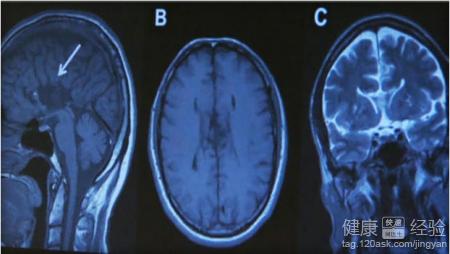

2患者現在的情況必須先觀察24小時,要觀察大腦是否有其它的不適,如果患者頭痛嚴重、視力等受到影響的,建議做腦電圖或是腦CT診斷疾病,防止有腦出血的現象,如查不能及時發現,會威脅患者的生命。